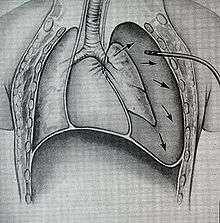

Treatment of TBI varies based on the location and severity of injury and whether the patient is stable or having trouble breathing,[2] but ensuring that the airway is patent so that the patient can breathe is always of paramount importance.[14] Ensuring an open airway and adequate ventilation may be difficult in people with TBI.[3] Intubation, one method to secure the airway, may be used to bypass a disruption in the airway in order to send air to the lungs.[3] If necessary, a tube can be placed into the uninjured bronchus, and a single lung can be ventilated.[3] If there is a penetrating injury to the neck through which air is escaping, the trachea may be intubated through the wound.[14] Multiple unsuccessful attempts at conventional (direct) laryngoscopy may threaten the airway, so alternative techniques to visualize the airway, such as fiberoptic or video laryngoscopy, may be employed to facilitate tracheal intubation.[14] If the upper trachea is injured, an incision can be made in the trachea (tracheotomy) or the cricothyroid membrane (cricothyrotomy, or cricothyroidotomy) in order to ensure an open airway.[6] However, cricothyrotomy may not be useful if the trachea is lacerated below the site of the artificial airway.[14] Tracheotomy is used sparingly because it can cause complications such as infections and narrowing of the trachea and larynx.[26] When it is impossible to establish a sufficient airway, or when complicated surgery must be performed, cardiopulmonary bypass may be used—blood is pumped out of the body, oxygenated by a machine, and pumped back in.[26] If a pneumothorax occurs, a chest tube may be inserted into the pleural cavity to remove the air.[19]

While TBI may be managed without surgery, surgical repair of the tear is considered standard in the treatment of most TBI.[3][27] It is required if a tear interferes with ventilation; if mediastinitis (inflammation of the tissues in the mid-chest) occurs; or if subcutaneous or mediastinal emphysema progresses rapidly;[3] or if air leak or large pneumothorax is persistent despite chest tube placement.[19] Other indications for surgery are a tear more than one third the circumference of the airway, tears with loss of tissue, and a need for positive pressure ventilation.[26] Damaged tissue around a rupture (e.g. torn or scarred tissue) may be removed in order to obtain clean edges that can be surgically repaired.[15] Debridement of damaged tissue can shorten the trachea by as much as 50%.[28] Repair of extensive tears can include sewing a flap of tissue taken from the membranes surrounding the heart or lungs (the pericardium and pleura, respectively) over the sutures to protect them.[2] When lung tissue is destroyed as a result of TBI complications, pneumonectomy or lobectomy (removal of a lung or of one lobe, respectively) may be required.[29] Pneumonectomy is avoided whenever possible due to the high rate of death associated with the procedure.[3] Surgery to repair a tear in the tracheobronchial tree can be successful even when it is performed months after the trauma, as can occur if the diagnosis of TBI is delayed.[3] When airway stenosis results after delayed diagnosis, surgery is similar to that performed after early diagnosis: the stenotic section is removed and the cut airway is repaired.[28]